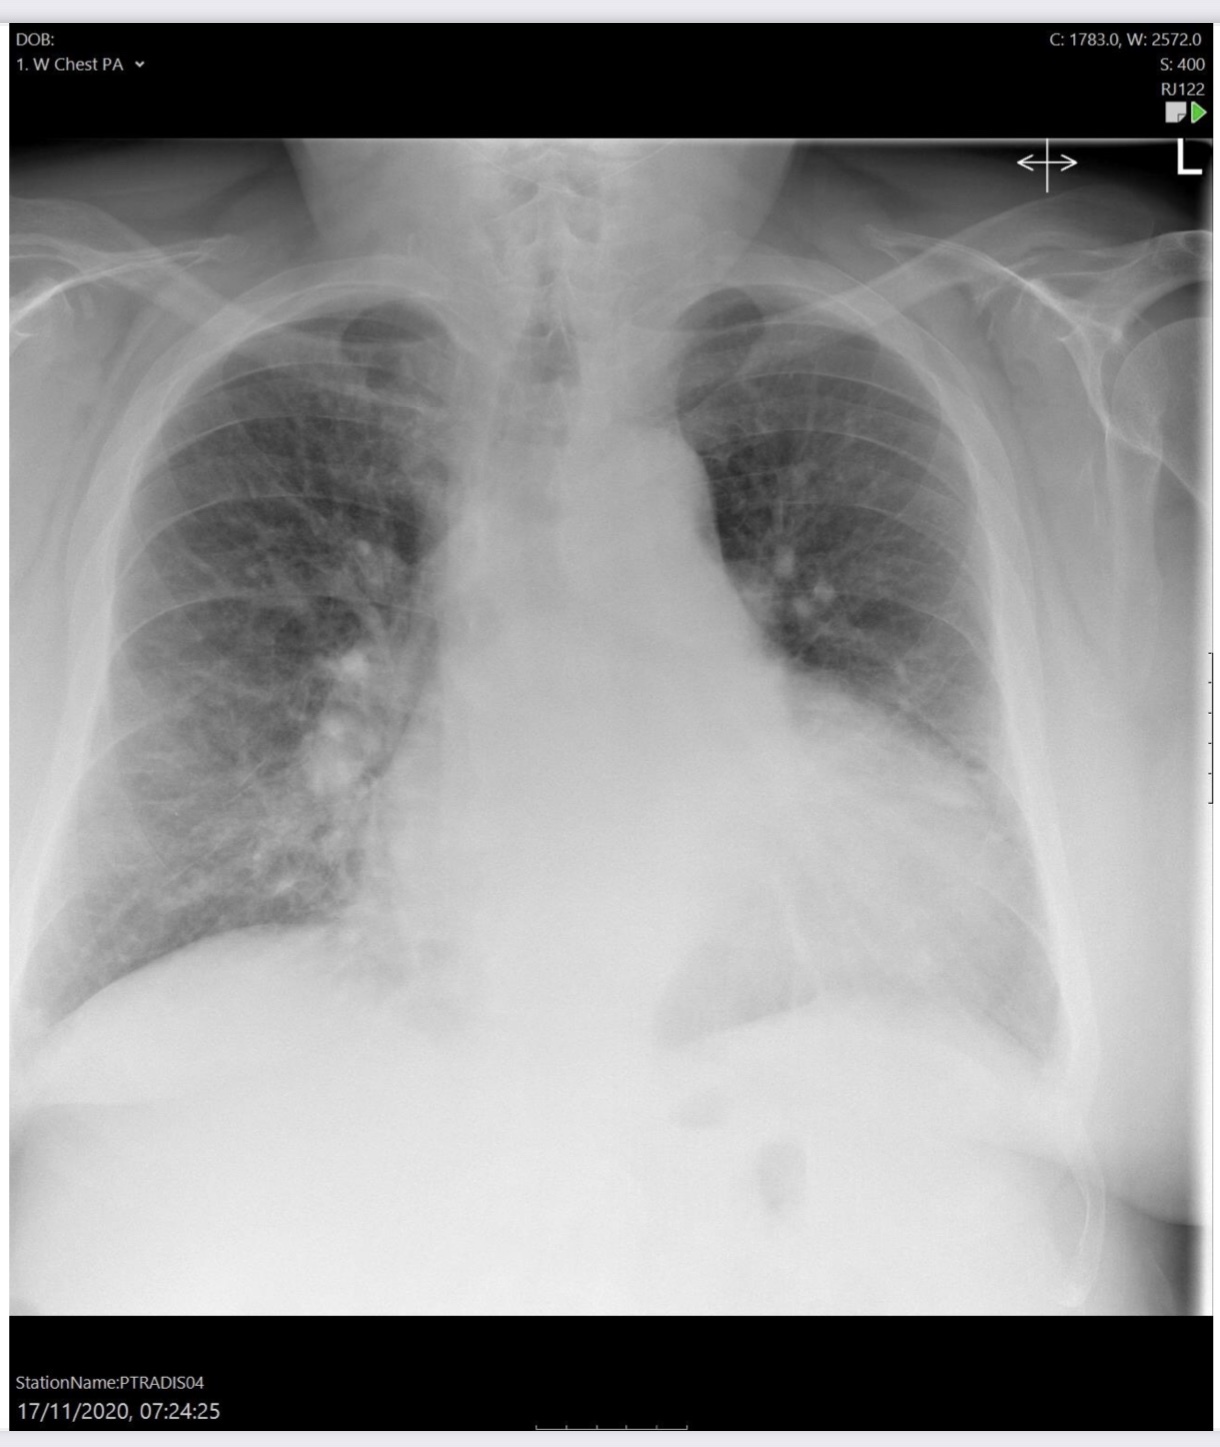

Heart failure

Alveolar oedema

Cardiomegaly (although AP so can’t assess properly)

Dilated upper lobe vessels

Pleuarl effusion